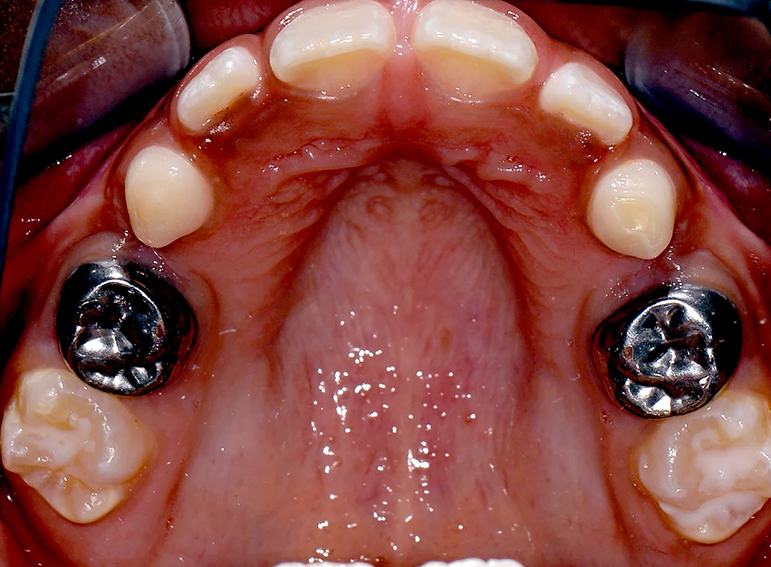

Hypoplastic primary molars: Placement of hall crowns, extraction of URD and ULD, composite restorations of LRD, LLD and…